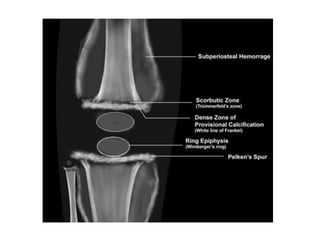

Xray findings

• White line of Fraenkel

• Wimberger’s sign

• Ground glass translucency of bone

• Thinned out cortices.

• Sub-periosteal haemorrhage

• Epiphyseal separation

• Pelkan spur ( Small bony spur protruding out of

the lateral border of the metaphysis at its

junction with epiphysis)

• Haemorrhages withinthe metaphysis interferes with osteoblastic tissue. • • Endochondral ossification proceeds normally as far as calcified cartilage – accumulates in large amounts • • Notable deficency of osteoblast and osteoclast • • Broadened layer of calcified cartilage • ( White line of fraenkel)

• Within theepiphysis itself, a zone of calcified cartilage accumulates about the bony centrum. • Encircling dense ring is known as Wimberger’s ring.

• Metaphysis inresponse to haemorrhage becomes extremely hyperemic. • • Resultant resorption of bone and failure of laying down of new bones. • • Extremely defficient ossification – appears as dark zones of radiolucency next to the white line.

Xray findings • Whiteline of Fraenkel • Wimberger’s sign • Ground glass translucency of bone • Thinned out cortices. • Sub-periosteal haemorrhage • Epiphyseal separation • Pelkan spur ( Small bony spur protruding out of the lateral border of the metaphysis at its junction with epiphysis)